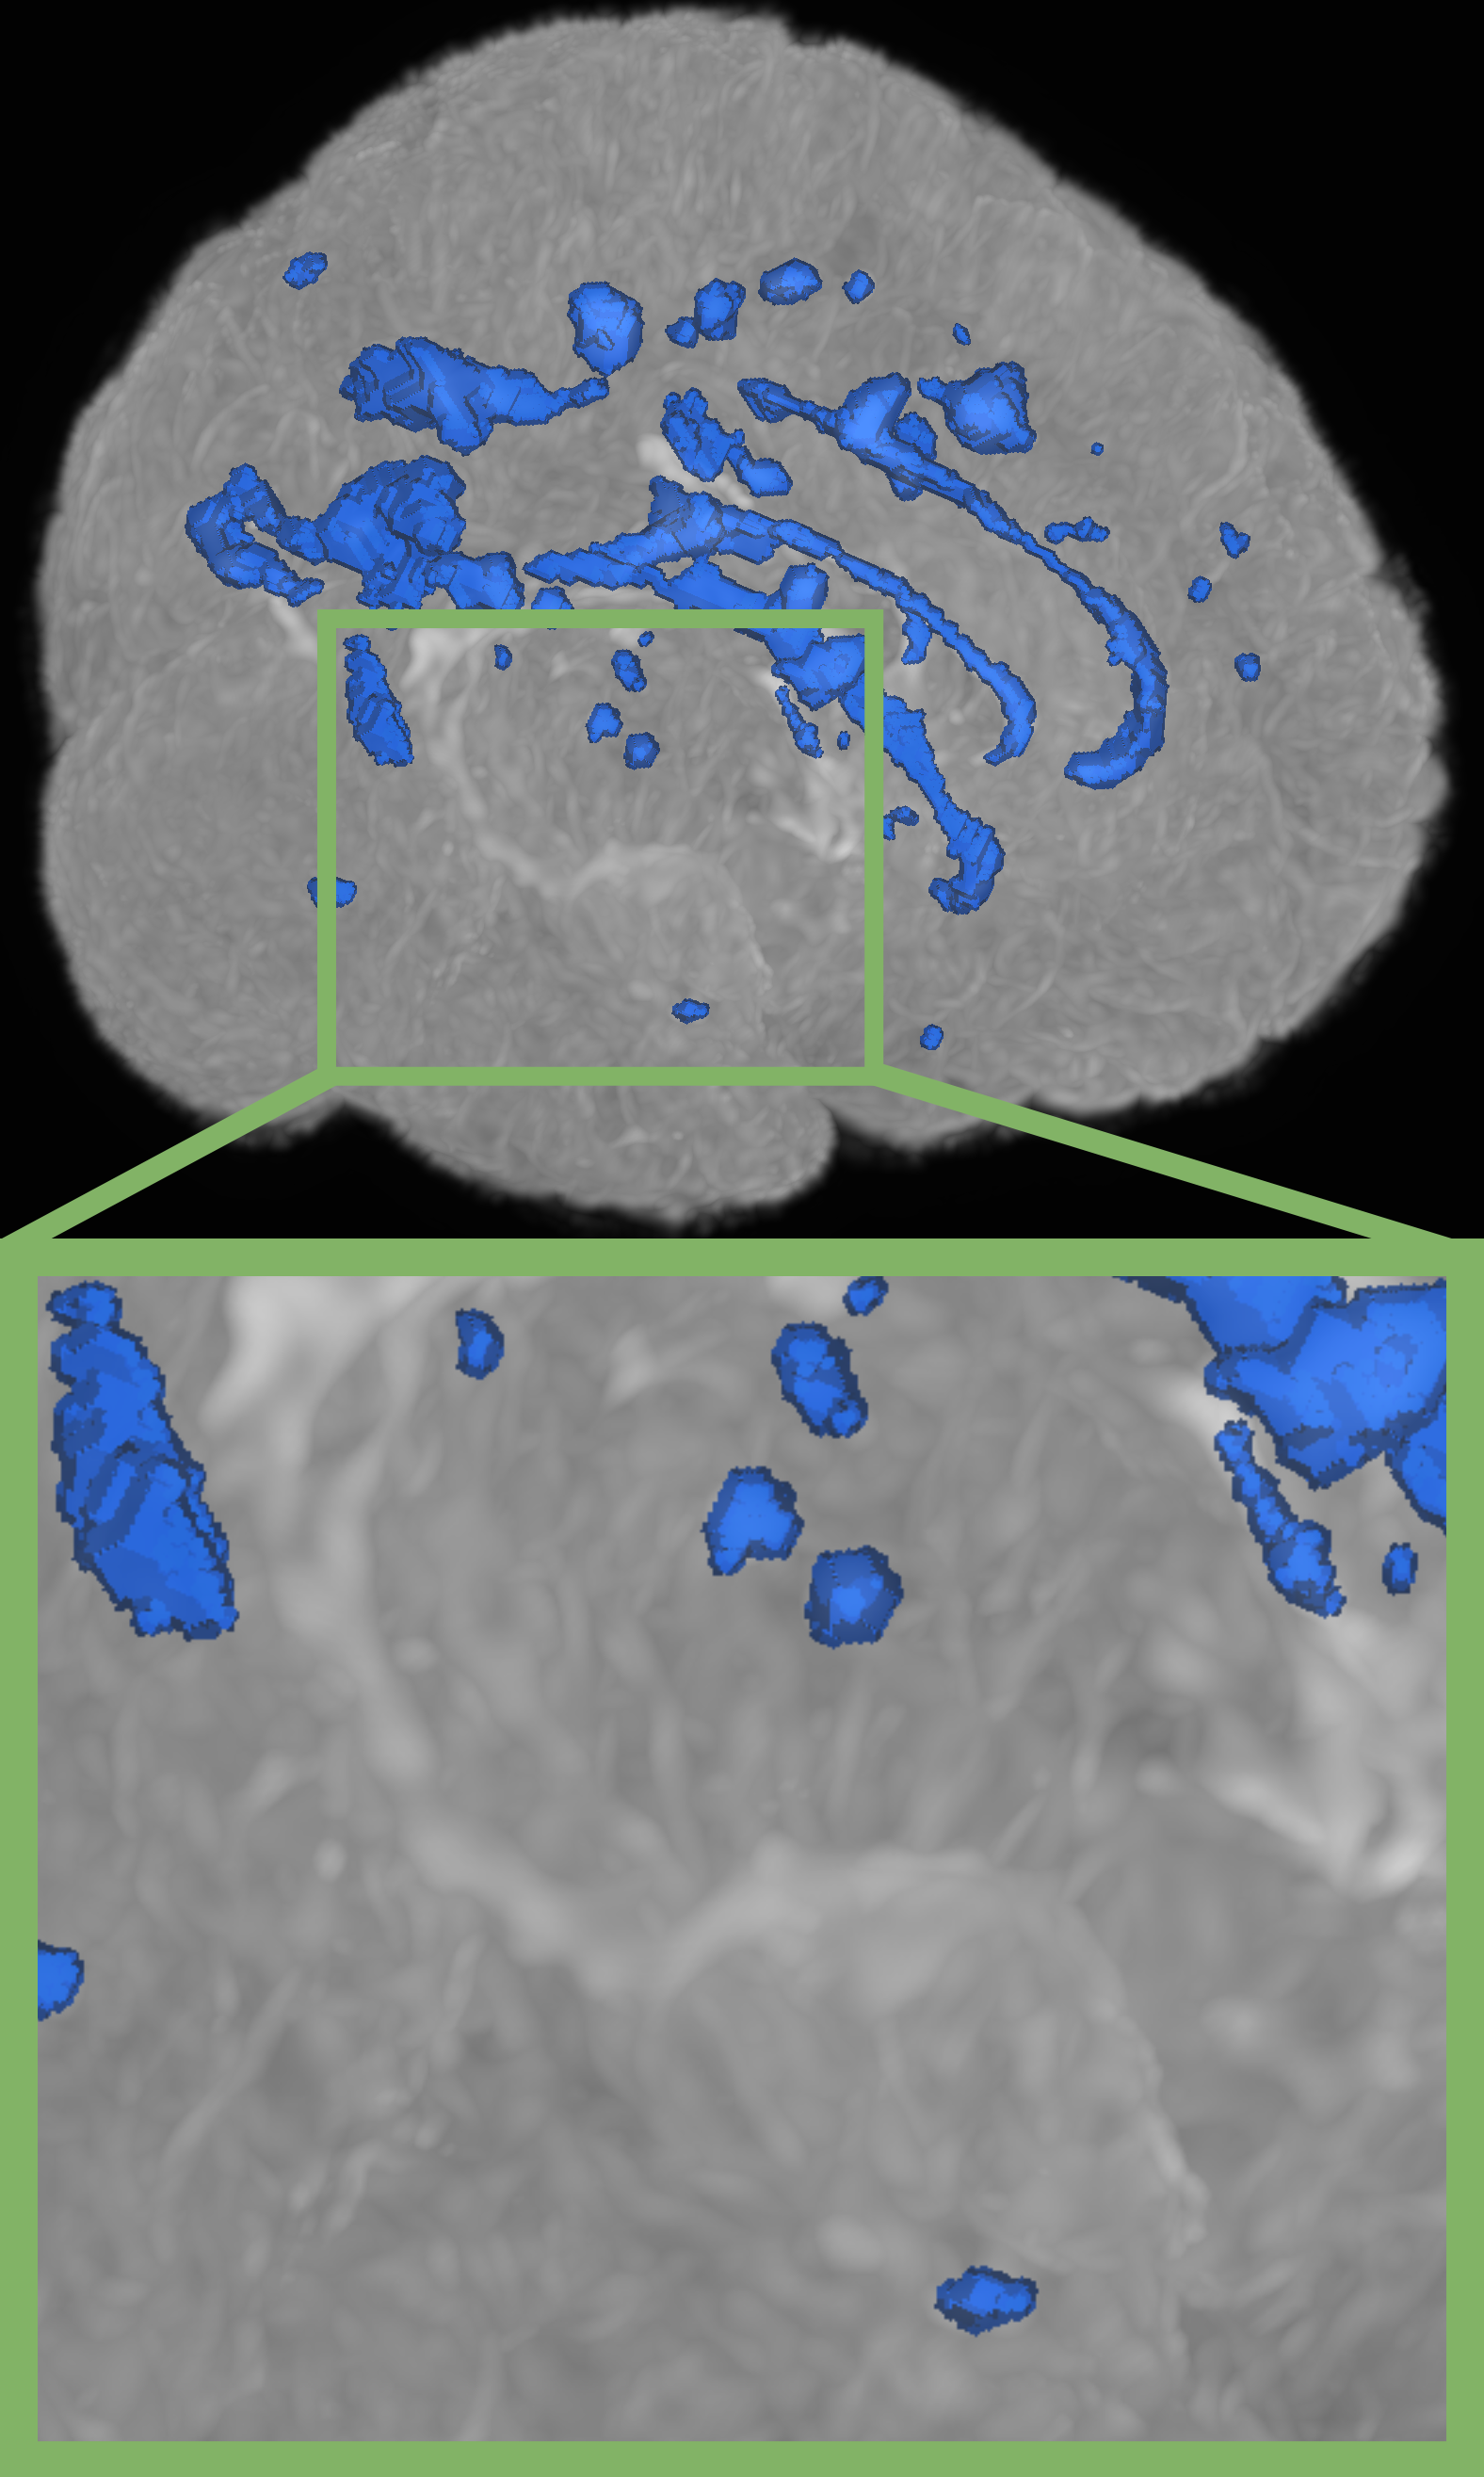

Refer to caption

(a) nnUNet[16]

(b) Szeskin et.al.[24]

(c) Difference Weighting (Ours)

(d) Ground Truth

Figure 2: Qualitative results on the Ljubljana dataset. Compared to related work, our proposed method demonstrates superior performance in volumetric delineation of MS lesions and successfully identifies lesions missed by other methods.

Table 2 illustrates SOTA performance against several established single and multi timepoint baselines on the Ljubljana dataset. We also show the generalizability of our best models on the ISBI 2015 dataset in Tab. 3 respectively. Figure 2 shows additional qualitative results on the Ljubljana dataset. Overall, we demonstrate the following findings:

Employing inductive bias via feature differences achieves SOTA performance: The integration of our novel Difference Weighting method further elevates the model’s performance, demonstrating a new state-of-the-art performance. Our proposed method improves upon nnUNet, as the best performing state-of-the-art model, by 1.45% in Dice score and 0.34mm in 95% Hausdorff distance. Notably, we see an increase of 2.01% in lesion-based F1 score, as the most important clinical metric, indicating that our approach better detects individual lesions. We also surpass the Longitudinal nnUNet indicating that the imposed inductive bias is superior over plain channel-wise concatenation.